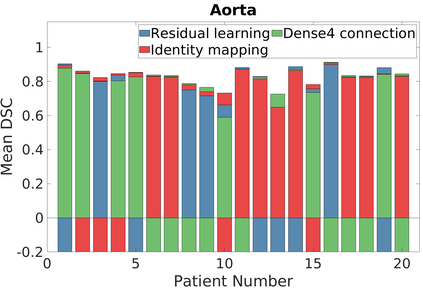

Deep Convolutional Neural Networks (DCNNs) are used extensively in biomedical image segmentation. However, current DCNNs usually use down sampling layers for increasing the receptive field and gaining abstract semantic information. These down sampling layers decrease the spatial dimension of feature maps, which can be detrimental to semantic image segmentation. Atrous convolution is an alternative for the down sampling layer. It increases the receptive field whilst maintains the spatial dimension of feature maps. In this paper, a method for effective atrous rate setting is proposed to achieve the largest and fully-covered receptive field with a minimum number of atrous convolutional layers. Furthermore, different atrous blocks, shortcut connections and normalization methods are explored to select the optimal network structure setting. These lead to a new and full-scale DCNN - Atrous Convolutional Neural Network (ACNN), which incorporates cascaded atrous II-blocks, residual learning and Fine Group Normalization (FGN). Application results of the proposed ACNN to Magnetic Resonance Imaging (MRI) and Computed Tomography (CT) image segmentation demonstrate that the proposed ACNN can achieve comparable segmentation Dice Similarity Coefficients (DSCs) to U-Net, optimized U-Net and hybrid network, but with significantly reduced trainable parameters due to the use of full-scale feature maps and therefore computationally is much more efficient for both the training and inference.